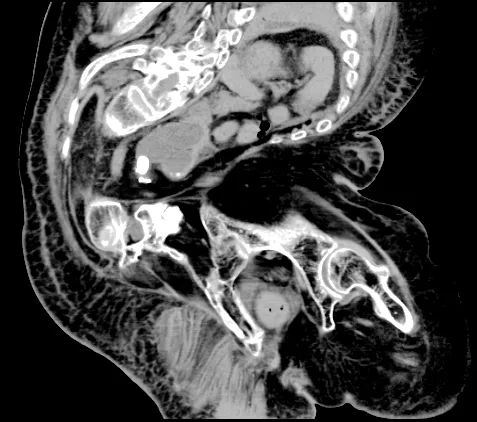

患者因“发现血肌酐升高1月余,发热1周”在我院肾内科住院治疗。住院期间行CT等检查明确肌酐升高、发热的原因是双侧输尿管存在结石梗阻。患者既往因小儿麻痹后遗症导致严重的脊柱侧弯畸形,直视下患者出现明显“驼背”,身体呈“折刀样”,X光平片下原本应该直立的脊柱呈“S”型改变,同时CT显示双肾明显异位、双侧输尿管明显扭曲,其中左肾甚至停留在脊柱偏右侧位置,与大血管十分贴近,给输尿管镜手术入镜及经皮肾手术穿刺带来极大困难和风险,稍有偏差就可能损伤到重要脏器及大血管。患者的脊柱侧弯畸形还合并有严重的胸廓畸形,畸形的胸廓导致肺和心脏的活动空间被大幅压缩,直接会引起心脏和肺的功能减退,麻醉过程中一旦出现意外,患者的心功能和肺功能衰竭会危及生命。不仅如此,患者还合并有重度贫血、高血压、脑萎缩、膀胱多发憩室等多种严重影响手术安全或操作的基础病。

▲患者右肾结石

▲患者左侧输尿管上段结石